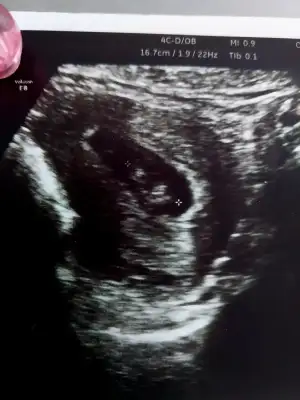

Canım ultrasonda niye 22 hafta 2 günlük yazıyor yanlış mı yazılmışBebişe nub a göre yorum yapabilecek var mı kızlarr aşırı merak ediyorum B BarbieveKen göreveebirde kalp atışı dk da 144 dedi araştırmalarıma göre 140 ın üstü kız yazıyor

ay öyle güzel oynuyordu ki pıtır pıtırdı eller ayakları

bence erkek ..benim de ultrasonda boyle görünüyodu irice.tahminimce erkektirNub u nasıl anlıyorsun net bir şekilde, bende intten cok baktim ama anlamıyorum, benimkinin burda nub belli mii B BarbieveKen